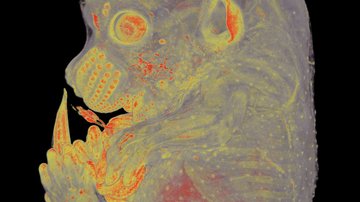

Müller M, Wetzel S, Köhn-Gaone J, Chalupsky K, Lüllmann-Rauch R, Barikbin R, Bergmann J, Wöhner B, Zbodakova O, Leuschner I, Gregor M, Tiegs G, Rose-John S, Sedlacek R, Tirnitz-Parker JE, Saftig P, Schmidt-Arras D A disintegrin and metalloprotease 10 (ADAM10) is a central regulator of murine liver tissue homeostasis. Oncotarget. 2016 Apr 5;7(14):17431-41. doi: 10.18632/oncotarget.7836.